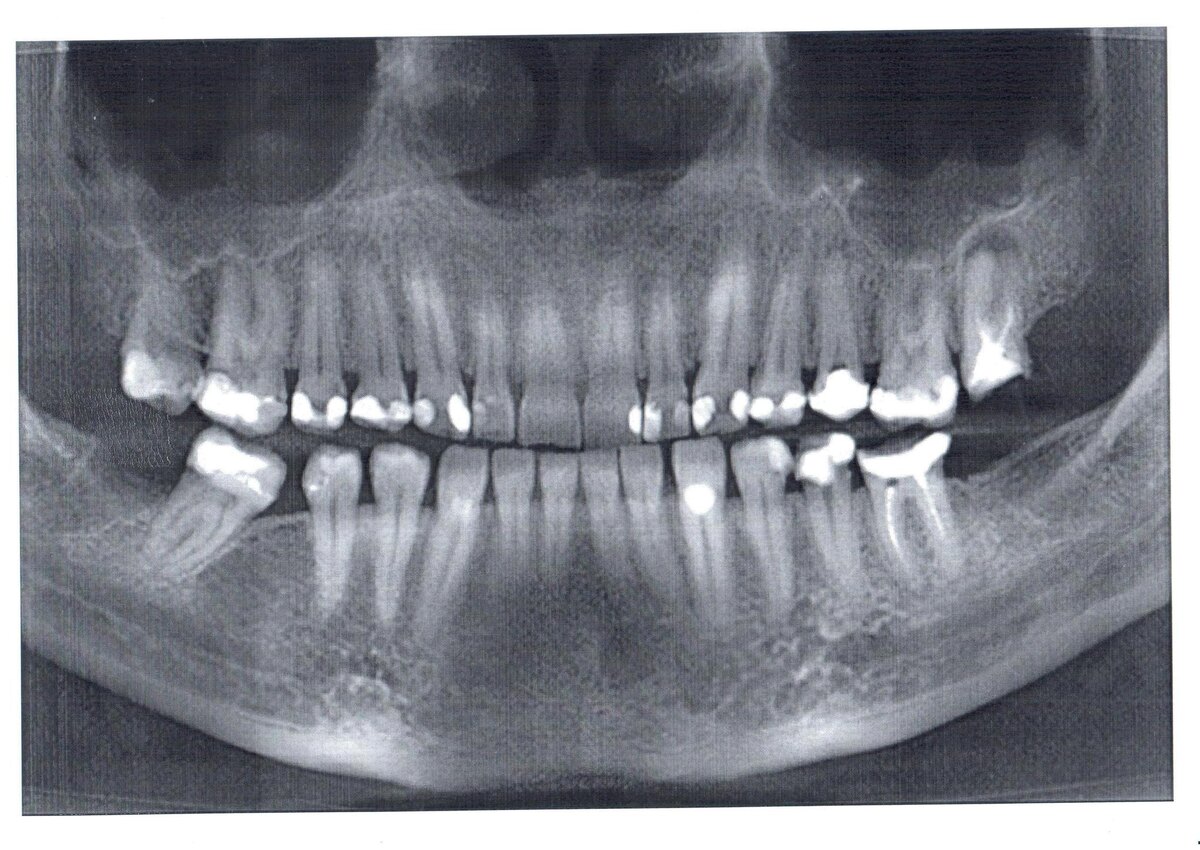

Испортились зубы после беременности

Во время беременности кальций из организма матери активно расходуется на построение скелета малыша. Если женщина не получает достаточного количества этого элемента с пищей, организм начинает "заимствовать" его из костей и зубов. Особенно интенсивно этот процесс идет во втором и третьем триместрах, когда у плода формируется костная ткань. При этом страдают не только зубы — недостаток кальция может привести к судорогам в ногах, ломкости ногтей и даже остеопорозу.

Однако винить только беременность не стоит. Часто проблемы с зубами возникают из-за гормональных изменений — повышенный уровень прогестерона делает десны более рыхлыми и уязвимыми для бактерий. Токсикоз усугубляет ситуацию: желудочная кислота разрушает эмаль, а частые перекусы создают благоприятную среду для кариеса. Многие женщины откладывают визит к стоматологу, опасаясь навредить ребенку, и в результате сталкиваются с серьезными проблемами.